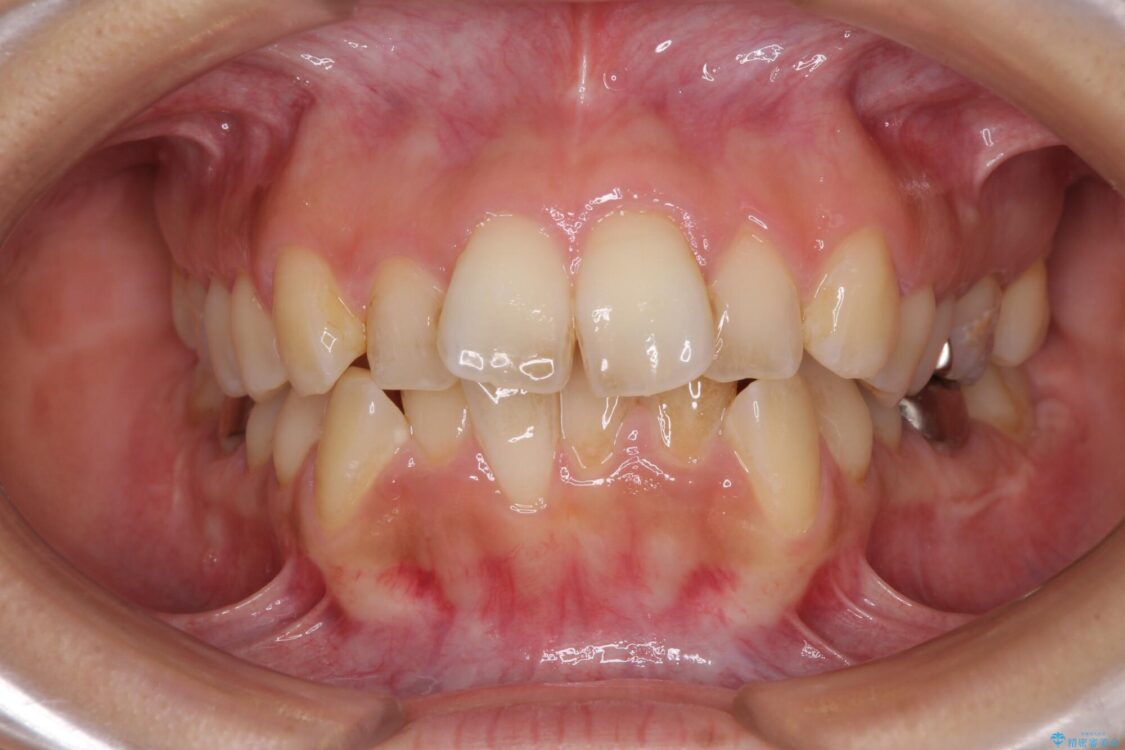

前歯のデコボコと上顎の前突感による口の閉じにくさを気にして来院された患者様です。

治療前

• デコボコと口元の突出感 ハーフリンガルでの抜歯矯正 治療前画像